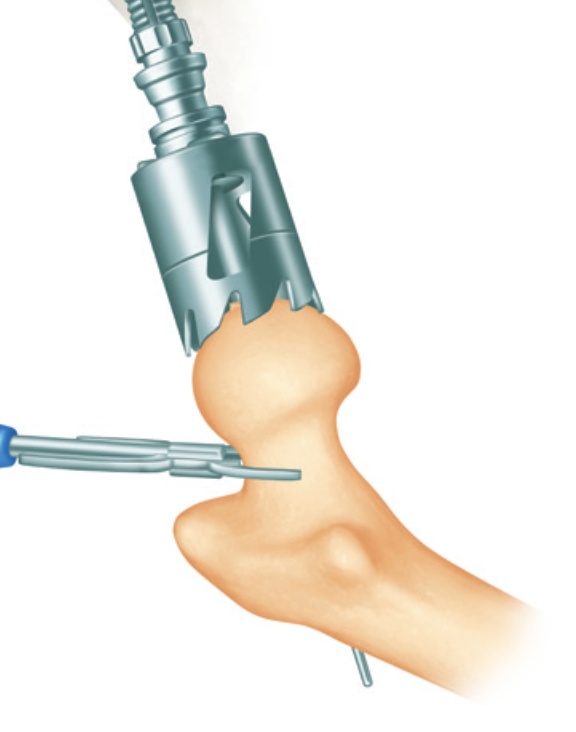

Femur - removal of femoral head cartilage and resurfacing with metal

Technique

Techniques

Birmingham Resurfacing

Smith&Nephew Birmingham Resurfacing PDF

Avoid

- notching

- varus

- open acetabulum

Technical issues

Femoral head notching